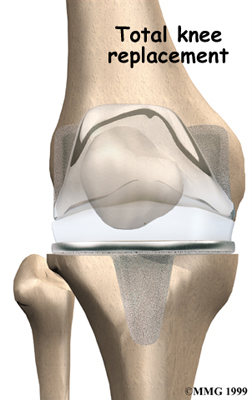

Artificial Knee Replacement

An artificial knee replacement is the ultimate solution for advanced knee OA.

Surgeons prefer not to put a new knee joint in patients younger than 60. This is because younger patients are generally more active and might put too much stress on the joint, causing it to loosen or even crack. A revision surgery to replace a damaged prosthesis is harder to do, has more possible complications, and is usually less successful than a first-time joint replacement surgery.

Related Document: FYZICAL Wayne's Guide to Artificial Joint Replacement of the Knee